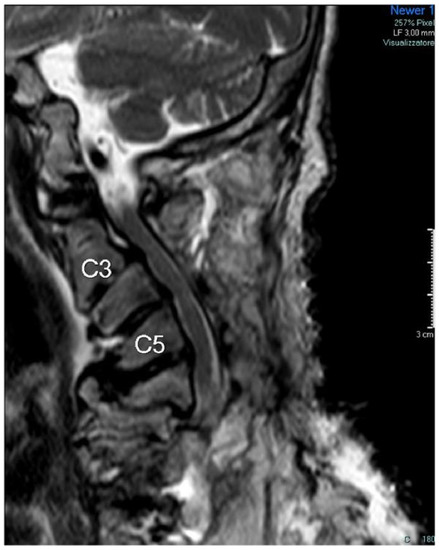

2. Case Description

Patient Details